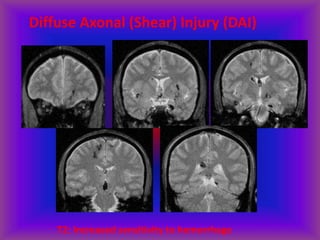

Diffuse Axonal (Shear) Injury (DAI)

Intra-axial Hemorrhage

T2: Reveals non-hemorrhagic lesions occult on CT

T2: Increased sensitivity to hemorrhage

• Tissues w/ differing elastic properties shear against each other,

tearing axons

• Caused by rapid deceleration/rotation of head

• Locations:

• Cerebral hemispheres near gray-white junction

• Basal ganglia

• Corpus callosum, especially splenium

• Dorsal brainstem

• High morbitity & mortality – common cause of post-traumatic

vegetative state

• Initial CT often normal despite poor GCS

• Lesions often non-hemorrhagic and seen only on MRI